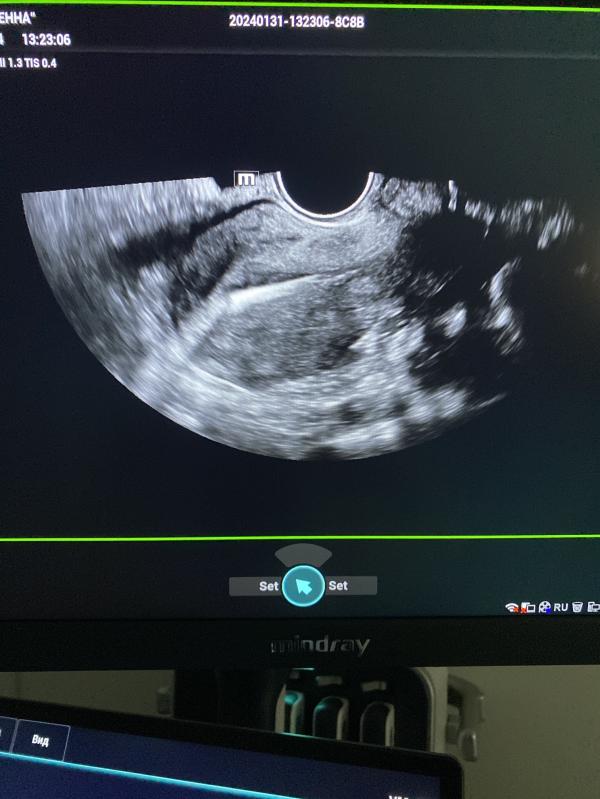

Спираль в полости матки ( белый стержень) после установки проходит 3 года. Стоит отлично 👍🏼.